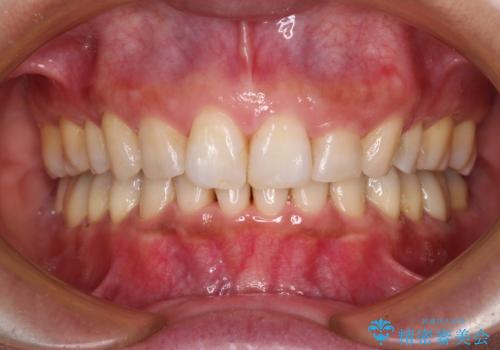

- 上の前歯の出っ歯と閉じにくい口元を気にして来院された患者様です。

口元を積極的に引っ込めるために、上顎左右の小臼歯1本ずつ抜歯することとしました。

ワイヤー装置にて矯正治療を行っていましたが、急な転勤で毎月の通院が難しくなってしまいました。

抜歯したスペースは概ね閉じていたので、インビザラインに切り替えて通院回数を減らし、治療を継続していくこととしました。

突出していた口元がスッキリと仕上がり、患者様には大変満足していただきました。